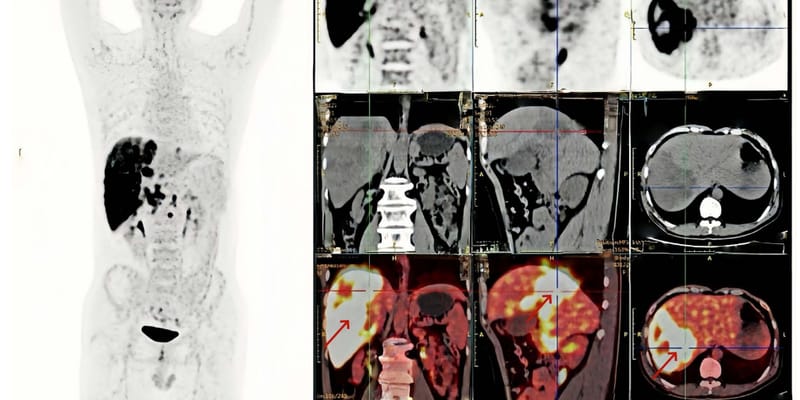

案例一:一名60岁的女性患者,诊断为复发性WHO 4级F3T3融合阳性胶质母细胞瘤。在接受标准放化疗后疾病进展,于2024年4月加入该试验。她在治疗的第1个周期就达到了部分缓解(PR),并在第13个周期实现了完全缓解(CR)。截至报告时,她已持续接受治疗超过19个周期,且治疗仍在进行中。

案例二:一名68岁的男性患者,诊断为IDH野生型、F3T3融合阳性的WHO 4级胶质母细胞瘤。在接受标准治疗后,于2024年10月入组试验。他在治疗的第8个周期时实现了部分缓解(PR)。